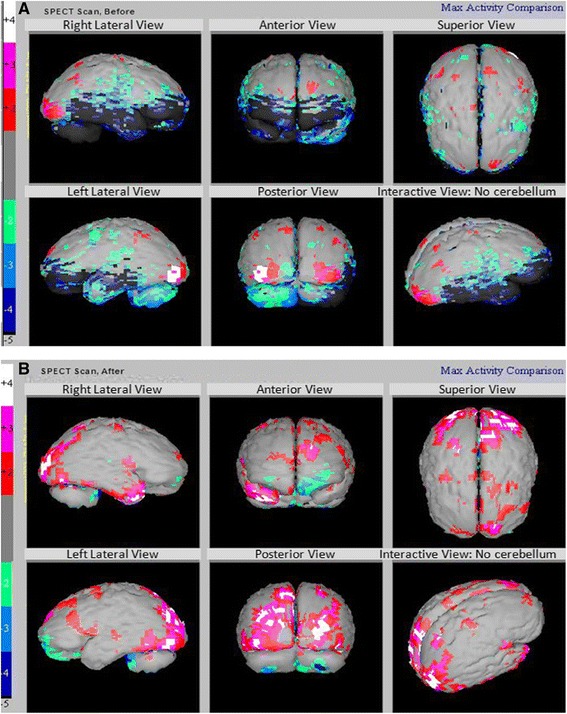

我們能夠在治療前后對所有患者進行SPECT掃描。患者的SPECT掃描顯示在接受hESC治療后灌注得到改善。我們一位患者的SPECT掃描報告如圖3A和B。

A)在接受hESC治療之前顯示灌注不足的區域。

B)接受hESC治療后灌注改善(黑色區域減少)。